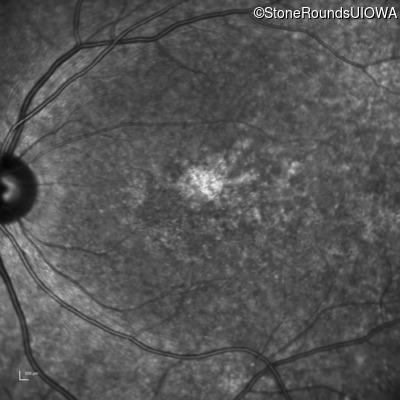

AR Stargardt Disease (IIA)

Age at visit: 32 years

This 32 year old man first noticed difficulty reading road signs when he was 21 years old.

AR Stargardt Disease ABCA4 Arg681Stop CGA>TGA Arg1860Trp CGG>TGG AR